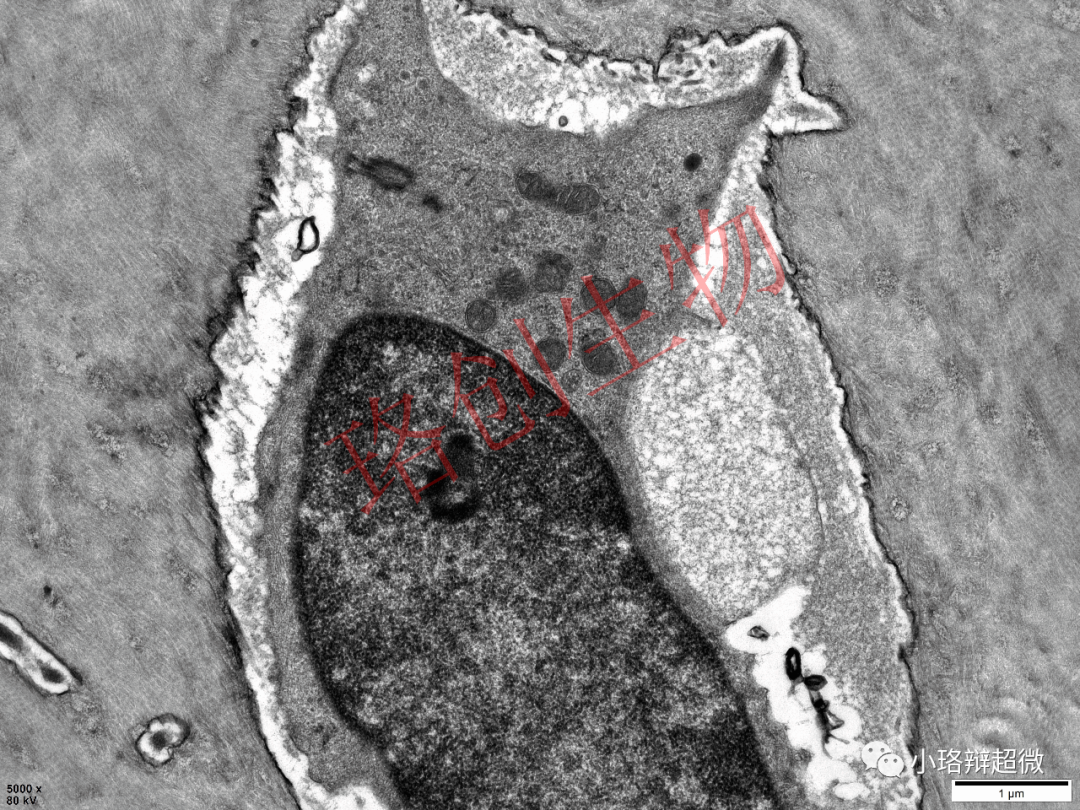

骨细胞所在腔隙为骨陷窝,突起所在腔隙为骨小管,相邻骨细胞通过突起的缝隙连接传递信息,骨陷窝-骨小管相互连通构成物质运输通道。

图片源于客户日常送检的骨组织标本,已获得客户知情同意,盗版必究